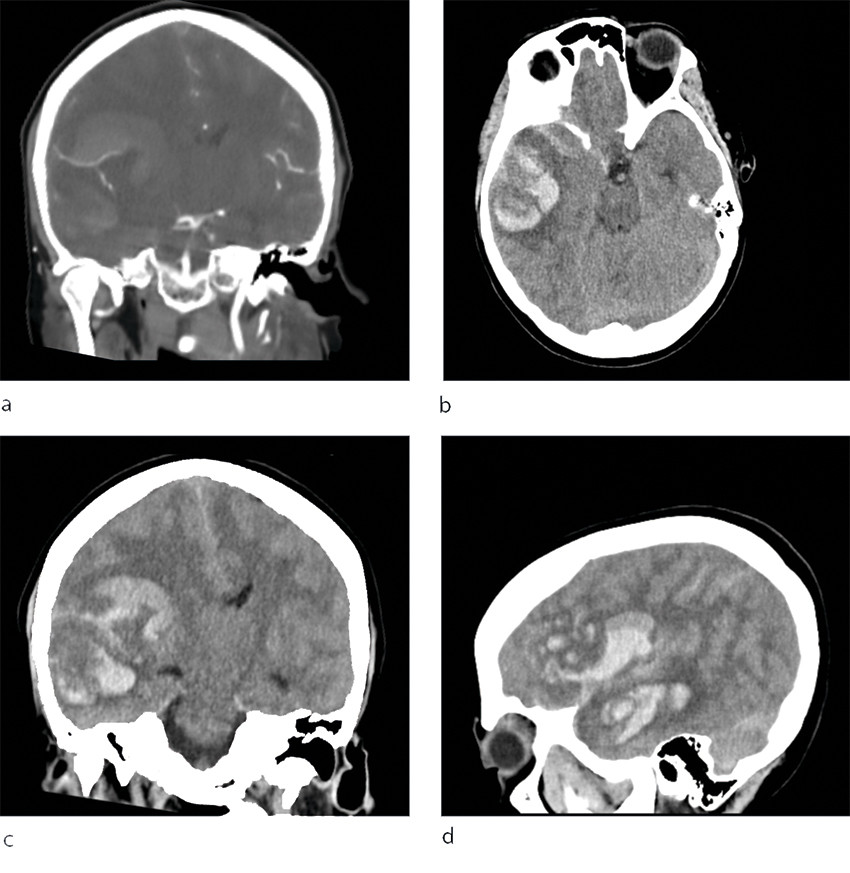

Intracerebral haemorrhage was strongly suspected, and the stroke alarm was triggered. A CT of the head was requisitioned and showed a large intracerebral haemorrhage in the right temporoparietal region in the supply region to the middle cerebral artery, incipient oedema with displacement of midline structures and severe compression of the right lateral ventricle. Both subarachnoid blood and some fresh blood were found in the brain parenchyma (Figure 1), but there was no visible blood in the ventricular system. CT angiography showed no evidence of an aneurysm.

Figure 1 CT of patient's head at a local hospital shows major parenchymal bleeding in the right hemisphere with breakthrough…

Figure 1 CT of patient's head at a local hospital shows major parenchymal bleeding in the right hemisphere with breakthrough into the subarachnoid space, b) axially, c) coronally and d) sagittally. There is a significant mass effect with midline displacement and incipient transtentorial herniation. Angiography (a) did not reveal focus of bleeding. The image was taken during the arterial contrast phase and is not suitable for ruling out cerebral venous thrombosis.

A few days after this incident, Oslo University Hospital, Rikshospitalet reported multiple cases of severe blood clots and bleeding in patients who had received an identical vaccine. These patients also had low platelet counts, and in these cases a link was found between the events and the vaccine (1). Since then, the condition has been referred to as vaccine-induced immune thrombotic thrombocytopenia (VITT), which is characterised by low platelet counts, thrombus formation and antibodies to PF4 (1, 5). In light of this knowledge, new investigations were carried out, and our patient was also found to have a tendency towards thrombus formation with small thrombi in the transverse sinus, frontal lobe and pulmonary artery. Antibodies to PF4 were also detected. Overall, there is therefore a strong indication that this was a case of VITT. Retrospectively, it has to be asked whether the bleeding seen on the CT images represented a venous haemorrhagic infarction similar to that seen in several patients at Rikshospitalet (1), and whether the bleeding component may have been predominant as a result of VITT. A venous infarction might explain the patient's headache.